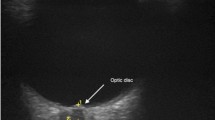

Optic neuritis frequently occurs in multiple sclerosis (MS), and shares several similarities with the optic neuritis of Leber's hereditary optic neuropathy (LHON), which is mainly due to maternally transmitted mitochondrial DNA (mtDNA) mutations. Our report shows for the first time that a mitochondrial DNA background could influence the clinical expression of MS. One European mtDNA haplogroup was found only in MS patients with optic neuritis but not in MS patients without visual symptoms. Therefore, we hypothesize that mtDNA haplogroup J might constitute a risk factor for optic neuritis occurrence when it is coincidentally associated with MS, but not be a risk factor for developing MS per se as suggested previously.